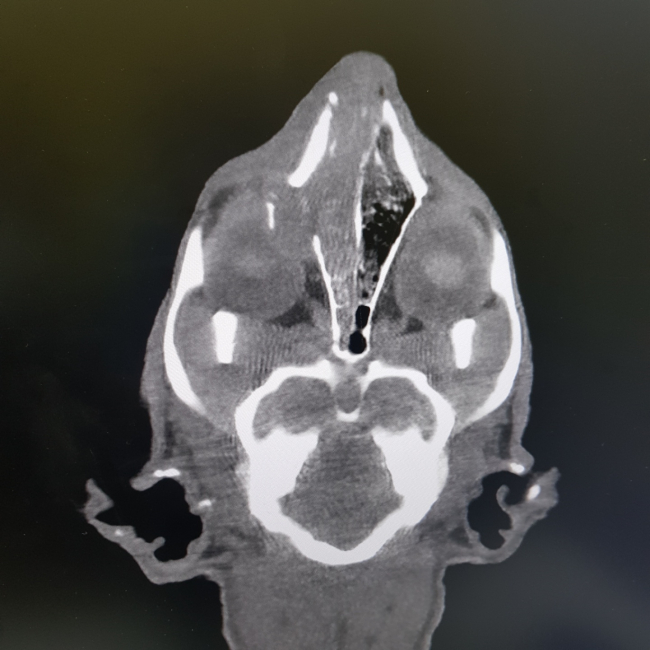

치료중 대상묘

![]()